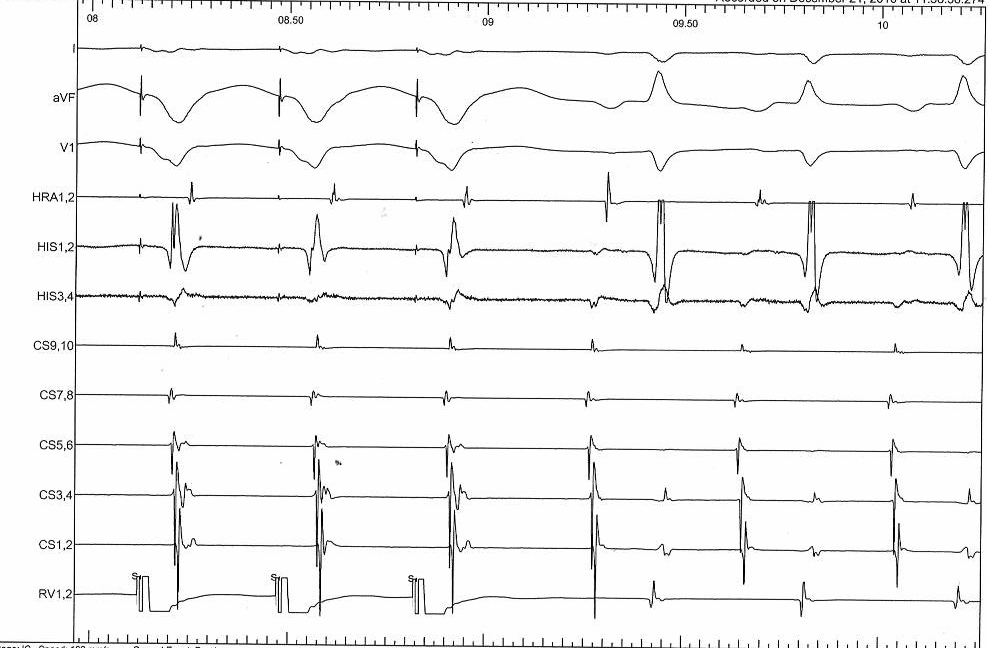

Narrow QRS tachycardia with VA > 70 ms and central VA

svt.jpg

Commonest Setting

• Regular narrow QRS tachycardia

• 1:1 VA

• Atrial activation central

• VA > 70 ms

SVT